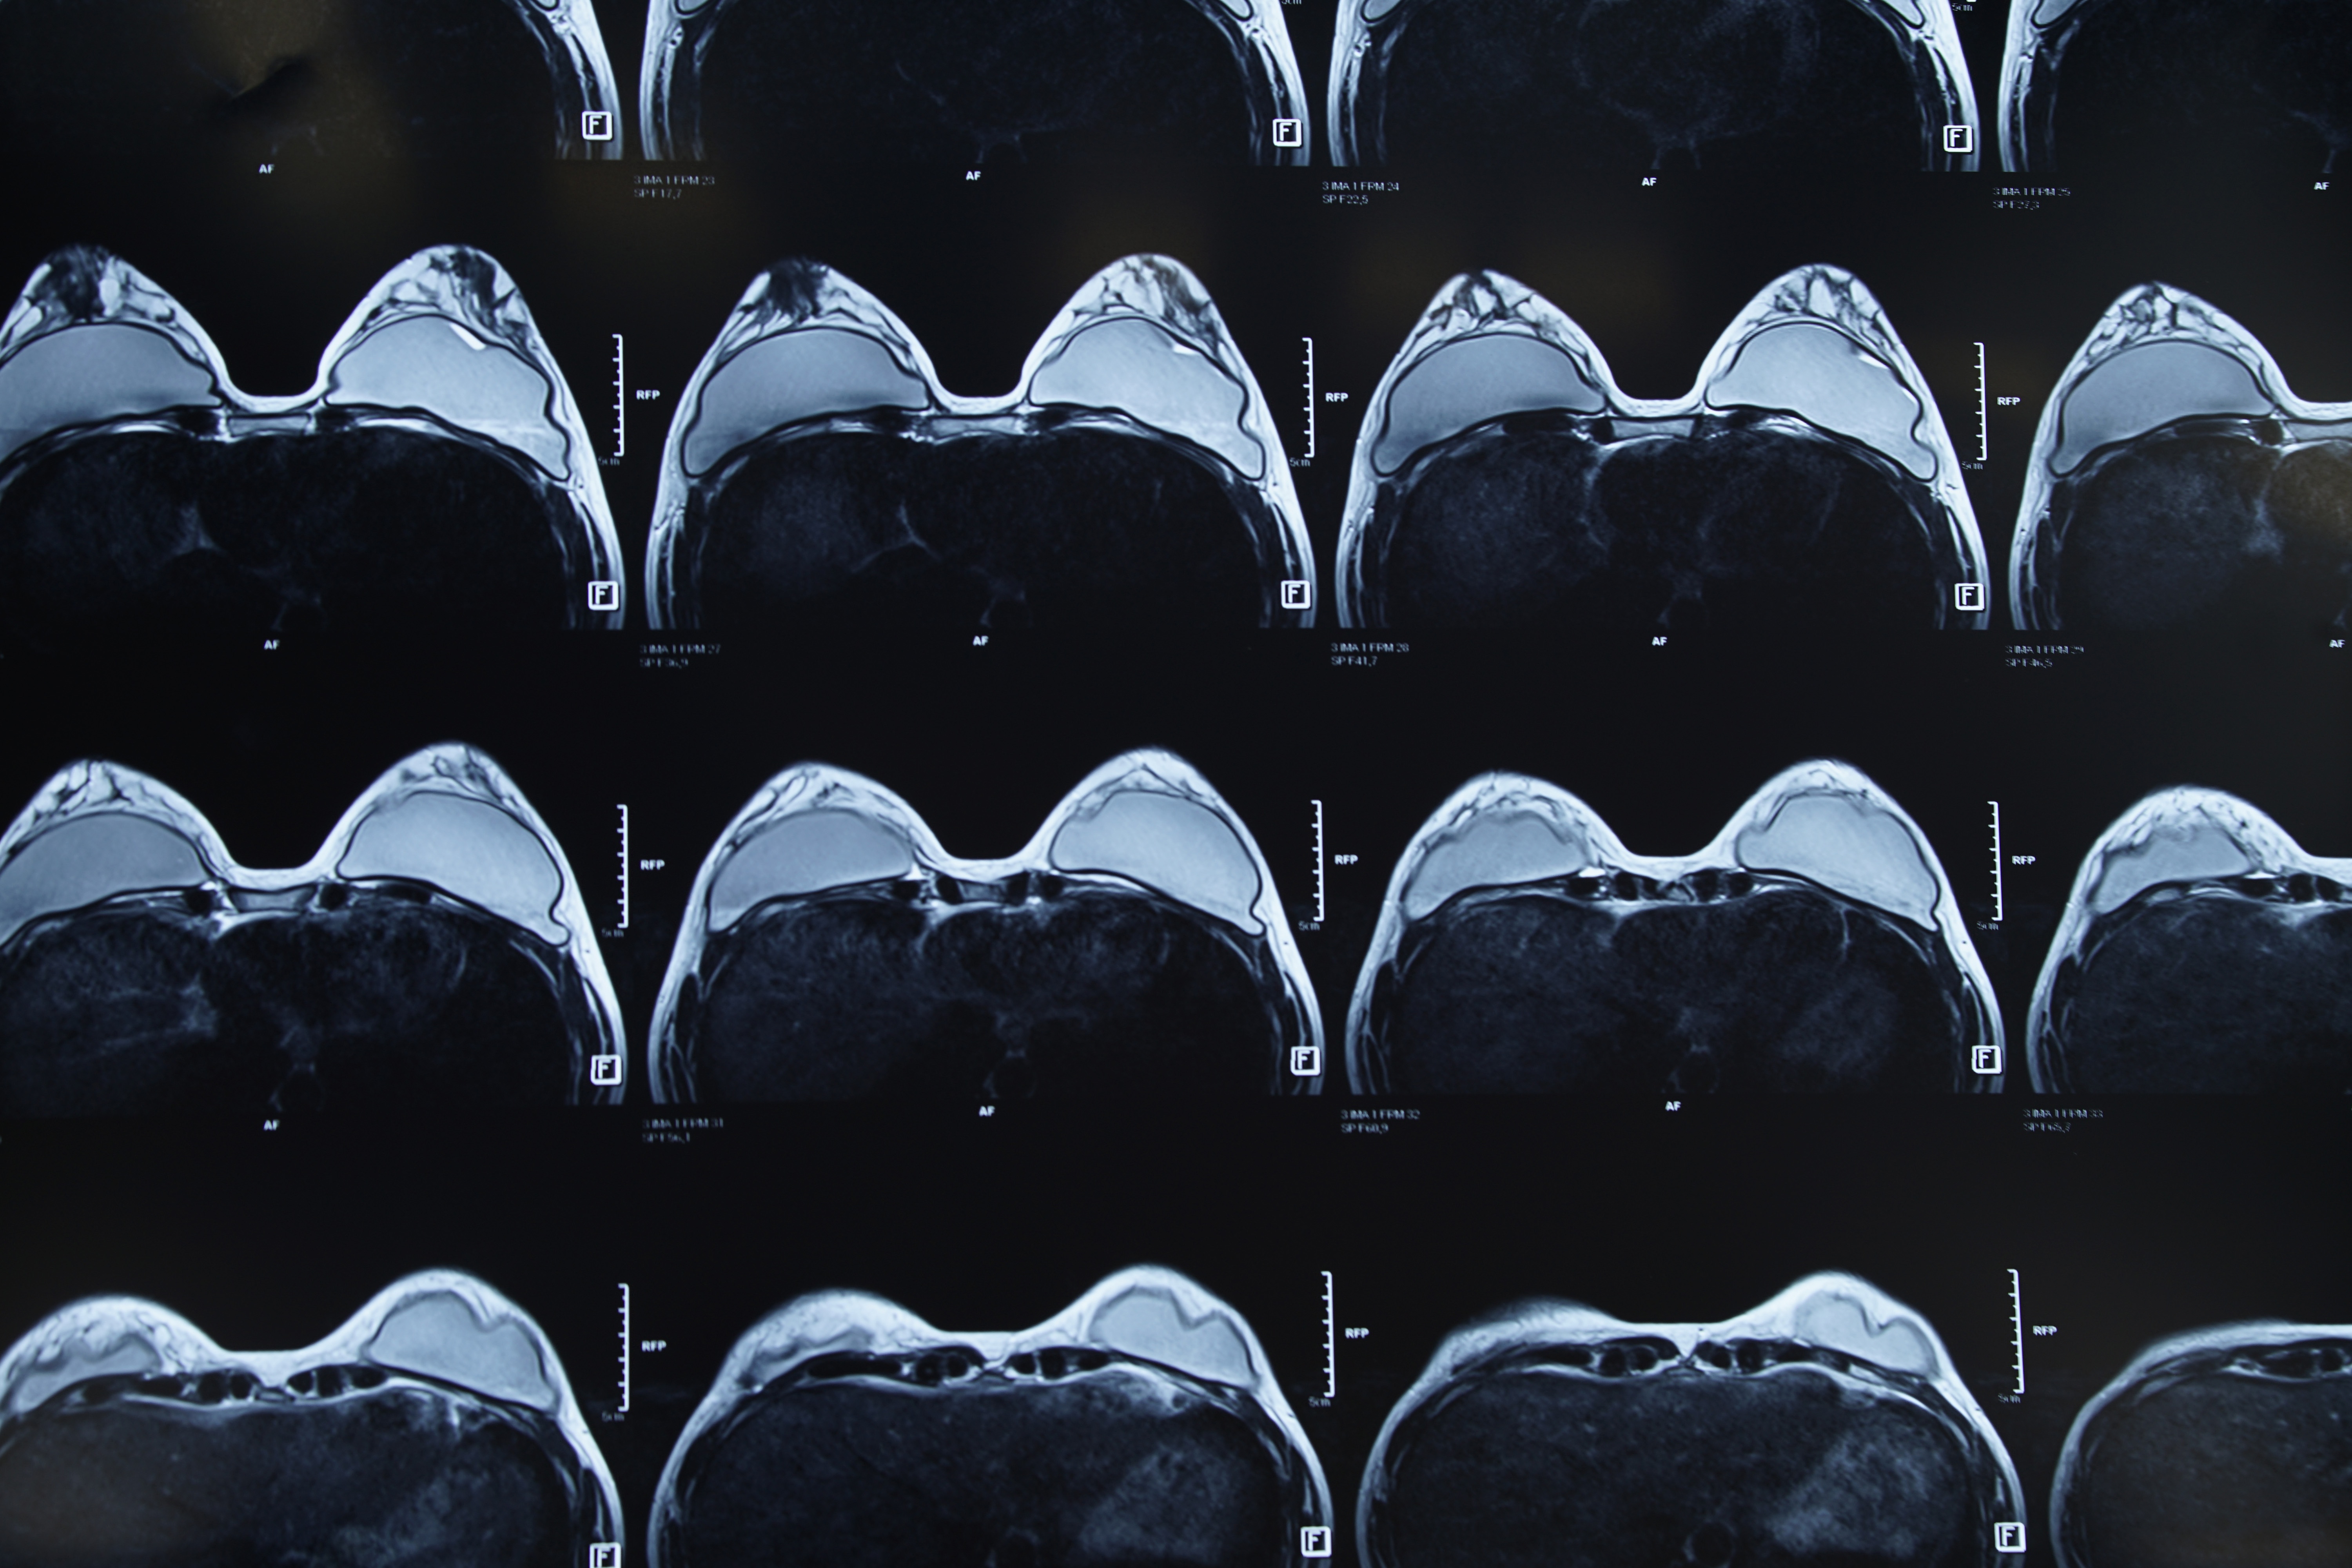

![]() ![]() |

| Cần 4-6 tháng sau phẫu thuật để ngực vào ”phom”. |